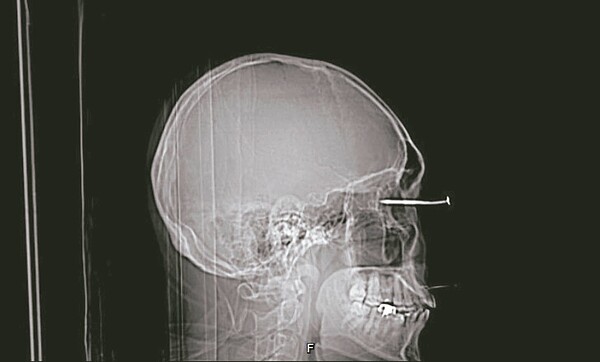

高醫外傷及重症外科主治醫師林佳蓉表示,遭鐵釘刺入的患者年約卅多歲,到醫院急診室時意識清楚,不過鐵釘已刺破眼球,立刻安排檢查及開刀事宜。

高醫眼科部主治醫師李學宇說,患者右眼被長度約六公分的鐵釘貫穿,由前至後造成眼角膜、水晶體、玻璃體、視網膜、脈絡膜、鞏膜等眼部組織受損。

院方表示,患者右眼被鐵釘貫穿後,在十二小時內就進行手術移除鐵釘,隨後用抗生素治療三天,防止發生感染,待數周後進行重建手術,雖然眼球外觀恢復看不出異樣,但因黃斑部區域受損,右眼視力仍未恢復正常,目前持續接受門診治療。